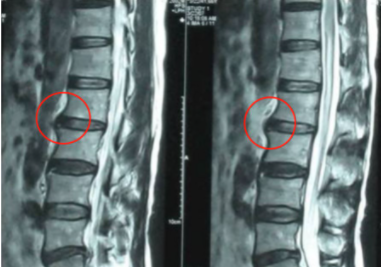

我是一名大学生,在2021年10月中旬,我被确诊为腰椎间盘右后突出,突出部分也压迫到了神经,造成右后臀部连接大腿处酸痛,影响到了我的日常生活。在拿到报告单的那一刻我还是有一点懵的,毕竟我才22岁,腰椎间盘突出这个病通常都是一些较为年长的人容易得,而我年纪轻轻却……

我越想越觉得以后自己的腰会不会废掉,到底需不需要通过手术把突出的那一块切掉呢?我带着疑惑来见了市中心医院运动康复科的医生,他第一句话就问我是不是有学舞蹈。